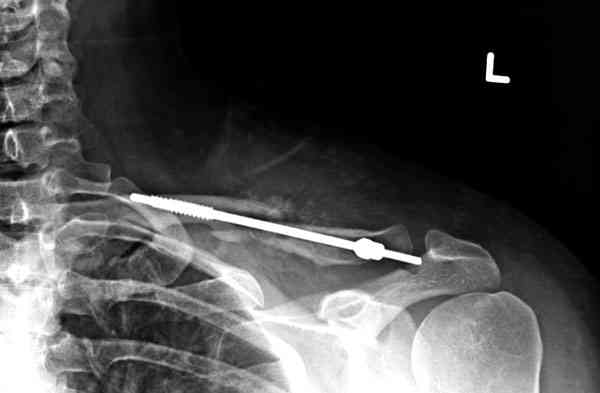

Судя по проекциям ключицы, очевидно разобщение фрагментов, чаще всего сопровождающееся интерпозицией платизмой. для 15 летнего пациента, категории физически активных пациентов выбрал бы оперативный метод( интрамедуллярно

винтом с частичной резьбой).

При выборе тактики лечения перелома ключицы всегда желательно иметь две взаимоперпендикулярные проекции: если фрагменты находятся в контакте друг с другом - лечение консервативное( достаточно косыночной повязки и спать с разведенными плечами на подушке между лопаток), разобщены - хирургия. Можно ждать 8-10 недель и импровизировать с кольцами, рамкой Чижина в это время - кому как удобно, я бы не стал.

Оценка положения костных фрагментов должна осуществляться по рентгенограммам, вы.полненным в двух проекциях. Стандартная ( и почему.то считающейся достаточной в большинстве наших лечебных учреждений) передне.задняя проекция дополняется шейной проекций под уг.лом 45°. Смещения: расхождение в поперечном направлении, отсутствие кортикального контакта, укорочение ключицы более 1,5 см . недопустимы и должны быть устранены (11,12).